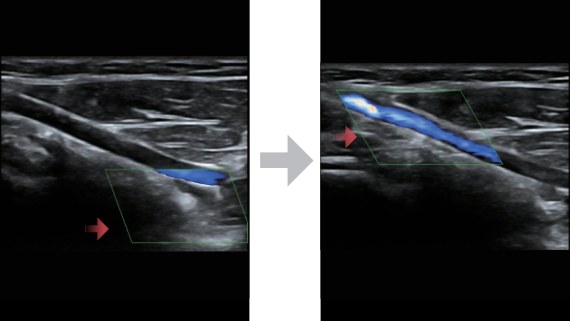

Klinische Bilder